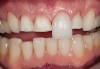

Figure 5  Image of minimal preparations prior to receiving bonded porcelain.

Figure 5

Figure 6  Two-year postoperative image of very conservative Category 1 bonded porcelain restorations.

Figure 6